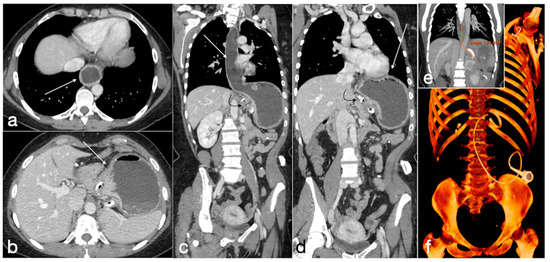

Figure 21. Patient 3. Huge hematoma with active bleeding. A 48-year-old patient developed abdominal pain and tachicardia suddenly after surgery for mini-gastric bypass. See the surgical suture (a, axial view). There is also a large hyperdense collection (b, coronal view, arrow) with active arterial bleeding (c, axial view, arrow), increasing conspicuously in the following portal-venous phase (d, MIP coronal view, straight arrow), arising from the gastroduodenal artery (branch of hepatic artery). It was promptly treated by gastroduodenal artery embolization (e,f).